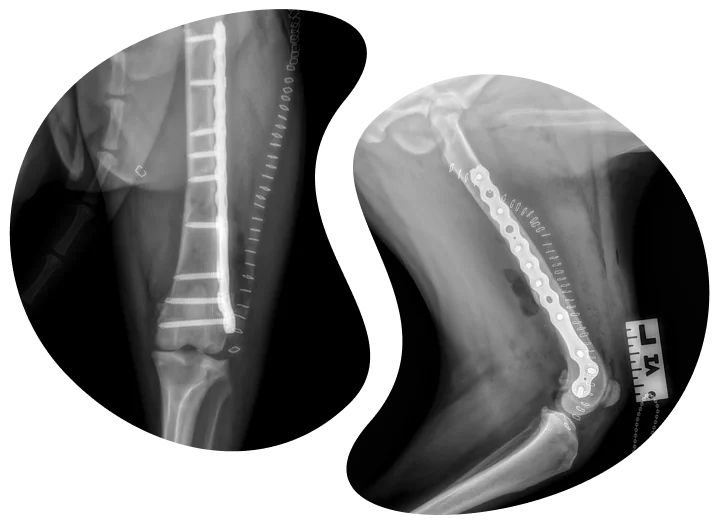

Veterinary ClinicBoard-Certified (DACVS-SA) surgeon, Dr. Hani Korani, provides advanced orthopedic & soft tissue surgery at clinics in San Francisco, Oakland, San Jose, and the Bay Area. Simple DVM referrals.